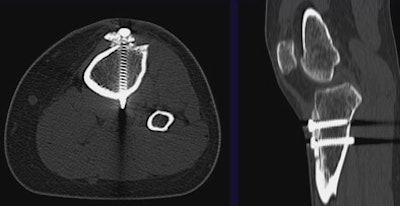

MDCT is also used to evaluate bony healing after orthopedic hardware is put in place. In a patient who had undergone a Fulkerson osteotomy for patellofemoral realignment, MDCT determined that bony union between the screwed-together tuburcle and underlying tibia had not yet been achieved.

![]() |

| MDCT can be used to evaluate bony healing following the placement of orthopedic hardware. The patient above underwent Fulkerson osteotomy for patellofemoral realignment. Two screws can be seen transversing the newly anteriorized tibial tubercle; however, bony union between the tuburcle and underlying tibia has not yet been achieved. |